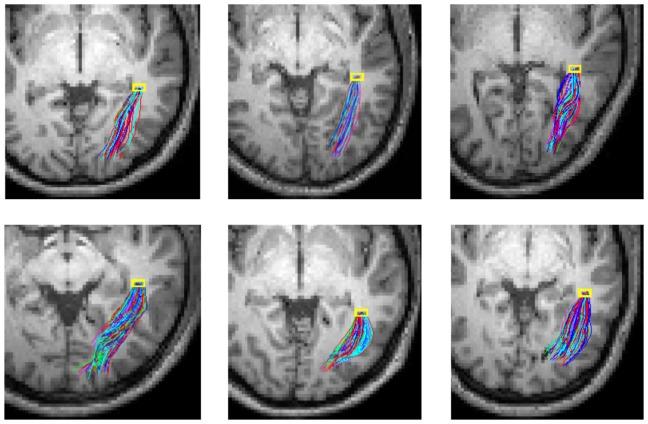

时空相关张量揭示了人类大脑中的功能结构。

Spatio-temporal correlation tensors reveal functional structure in human brain.

Resting state functional magnetic resonance imaging (fMRI) has been commonly used to measure functional connectivity between cortical regions, while diffusion tensor imaging (DTI) can be used to characterize structural connectivity of white matter tracts. In principle combining resting state fMRI and DTI data could allow characterization of structure-function relations of distributed neural networks. However, due to differences in the biophysical origins of their signals and in the tissues to which they apply, there has been no direct integration of these techniques to date. We demonstrate that MRI signal variations and power spectra in a resting state are largely comparable between gray matter and white matter, that there are temporal correlations of fMRI signals that persist over long distances within distinct white matter structures, and that neighboring intervoxel correlations of low frequency resting state signals showed distinct anisotropy in many regions. These observations suggest that MRI signal variations from within white matter in a resting state may convey similar information as their corresponding fluctuations of MRI signals in gray matter. We thus derive a local spatio-temporal correlation tensor which captures directional variations of resting-state correlations and which reveals distinct structures in both white and gray matter. This novel concept is illustrated with in vivo experiments in a resting state, which demonstrate the potential of the technique for mapping the functional structure of neural networks and for direct integration of structure-function relations in the human brain.

静息态功能磁共振成像(fMRI)已被广泛用于测量皮质区域之间的功能连接,而扩散张量成像(DTI)可用于表征白质束的结构连接。原则上,结合静息态fMRI和DTI数据可以表征分布式神经网络的结构-功能关系。然而,由于它们信号的生物物理起源以及所应用组织的差异,迄今为止这些技术尚未直接整合。我们证明,在静息状态下,灰质和白质之间的MRI信号变化和功率谱在很大程度上是可比的,在不同的白质结构内,fMRI信号存在长时间持续的时间相关性,并且低频静息态信号的相邻体素间相关性在许多区域表现出明显的各向异性。这些观察结果表明,静息状态下白质内的MRI信号变化可能与其在灰质中相应的MRI信号波动传达相似的信息。因此,我们推导了一个局部时空相关张量,它捕获静息态相关性的方向变化,并揭示了白质和灰质中的独特结构。这一新颖概念通过静息状态下的体内实验得到了说明,这些实验证明了该技术在绘制神经网络功能结构以及直接整合人类大脑结构-功能关系方面的潜力。